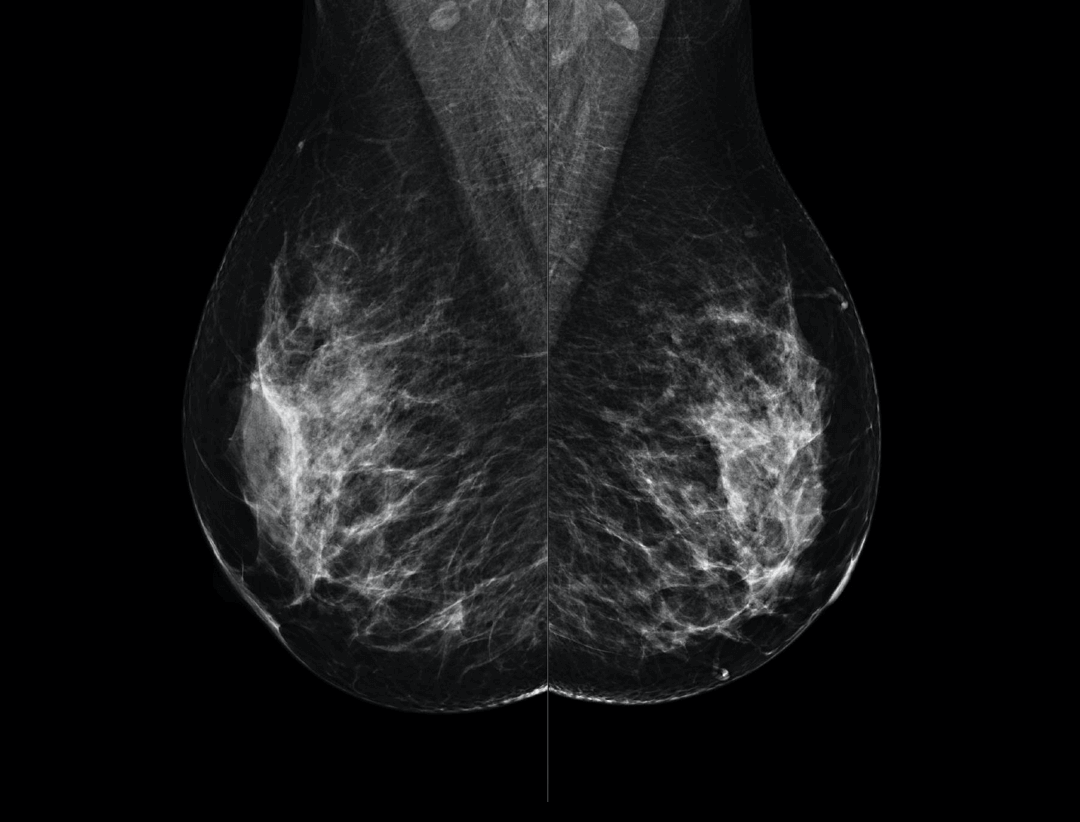

High Resolution Low Dose Imaging

Large coverage amorphous-silicon (a-Si) flat panel detector featuring an optimized active matrix array provides high spatial resolution and high image acquisition speed at a lower dose.

High performance tungsten target X-ray tube offers high resolution image for both dense and fatty breast densities.

Intelligntly detects breast density and thickness, then auto selects the appropriate filter combination.